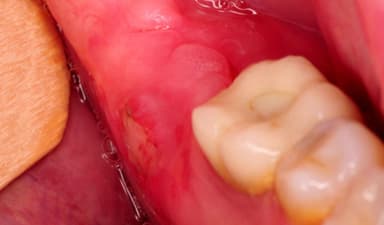

2.3. Viêm lợi trùm

Đây là một trong những nguyên nhân phổ biến nhất gây sưng nướu răng khôn. Khi răng khôn mới nhú hoặc mọc chưa hoàn toàn, lớp lợi phía trên có thể phủ trùm lên một phần thân răng, tạo thành một túi lợi nhỏ gọi là lợi trùm. Trong điều kiện này, thức ăn và vi khuẩn rất dễ mắc kẹt bên trong, gây viêm nhiễm. Triệu chứng đặc trưng gồm: sưng đau dữ dội vùng nướu, đỏ và nóng tại chỗ, kèm theo cảm giác khó há miệng, sốt nhẹ, nổi hạch. Nếu không được điều trị, viêm lợi trùm có thể tái phát nhiều lần và dẫn đến nhiễm trùng lan rộng.